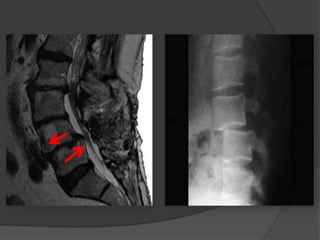

Diagnostico  Rx perfilse aprecia el desplazamiento de la L5  las proyecciones oblicuas se pone al descubierto la falta, de sustancia ósea a nivel del istmo.  TAC  RMN  Centellograma

 Rx perfil se aprecia el desplazamiento de la L5

 las proyecciones oblicuas se pone al

descubierto la falta, de sustancia ósea a nivel

 TAC

 RMN